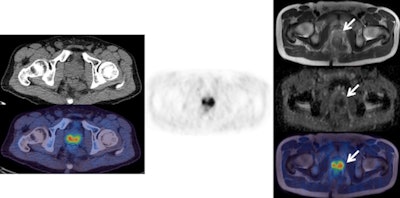

![Left: F-18 choline PET/CT (CT top and fused PET/CT bottom). Center: F-18 choline PET. Right: MRI (from top to bottom: T1, b900 diffusion-weighted image [DWI], apparent diffusion coefficient [ADC] map, fused PET/T1 MRI). These images show an enlarged choline-avid left pelvic lymph node in a man with high-risk Gleason 4+5 prostate cancer. This is clearly seen (arrow) on the PET/CT images, as well as on all the MRI sequences (high signal on b900 and restricted diffusion on ADC map). There is a small equivocal focus of uptake on the PET scan in the right side of the pelvis (arrow head), but it is difficult to confirm this is a lymph node on the CT and fused PET/CT images. The MRI sequences confirm a small lymph node with high signal on b900 DWI and restricted diffusion on ADC map (arrowhead). This case shows how the superior tissue contrast and anatomical resolution of MRI sequences allow a better definition of the cause of the right-sided pelvic PET activity and a much more confident diagnosis of right as well as left lymph node involvement. All images courtesy of Dr. Gary Cook.](https://img.auntminnie.com/files/base/smg/all/image/2016/03/am.2016_03_04_16_05_50_348_2016_03_05_ECR_Today_PET-MRI1.png?auto=format%2Ccompress&fit=max&q=70&w=400)